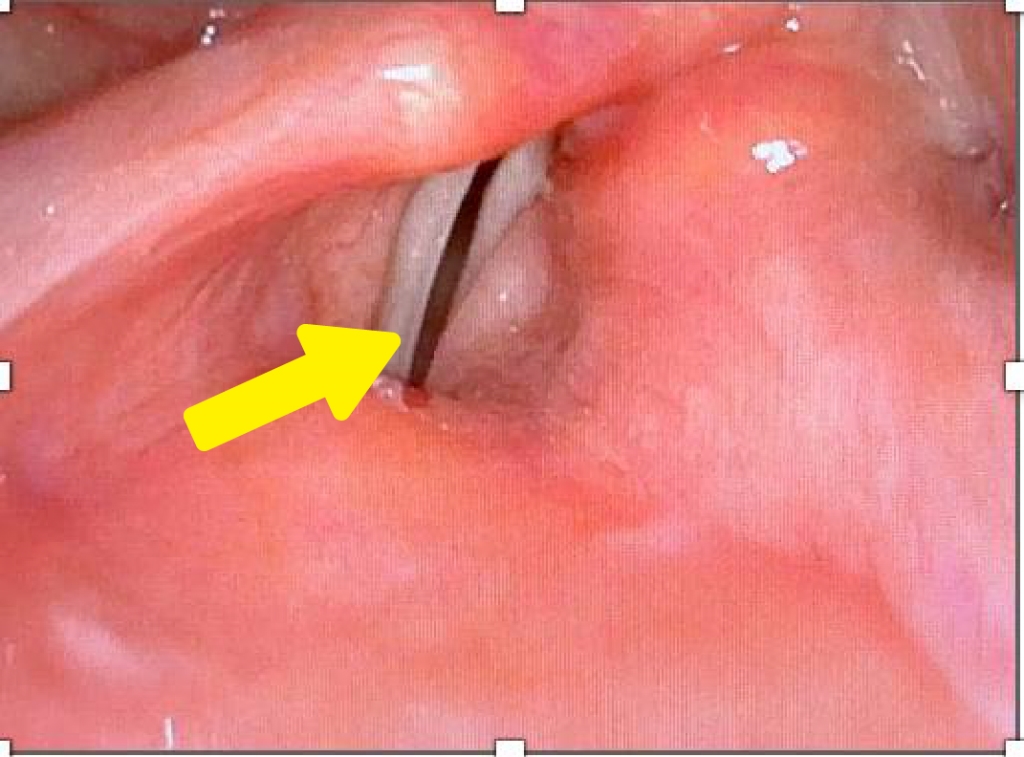

馬偕紀念醫院耳鼻喉頭頸部喉科主任醫師謝麗君指出,單側聲帶麻痺約占嗓音障礙患者的一成,其中二至三成原因不明,常見症狀包括聲音沙啞、講話氣音、發聲費力、音量變小,嚴重者還可能出現嗆咳、吞嚥困難及吸入性肺炎。急性期若採取保守嗓音及行為治療無明顯改善或是急需用聲者,可考慮接受聲帶注射手術,倘若聲帶麻痺已永久無法恢復,則可考慮甲狀軟骨成形術等治療。

謝麗君表示,「可調式甲狀軟骨成形術」是新一代的技術,與傳統甲狀軟骨成形術受限於醫師技術、植入物無法即時調整、術後也無法微調的缺點相比,可調式甲狀軟骨成形術的優點是患者在術中保持清醒,依患者的發聲情況予以微調,手術時間平均2小時,若覺得手術時的聲音調整不理想,還可以在術後回門診時微調,患者恢復期短、效果持久,不需特別復健與保養,為單側聲帶麻痹患者提供更富有彈性的治療新選項。